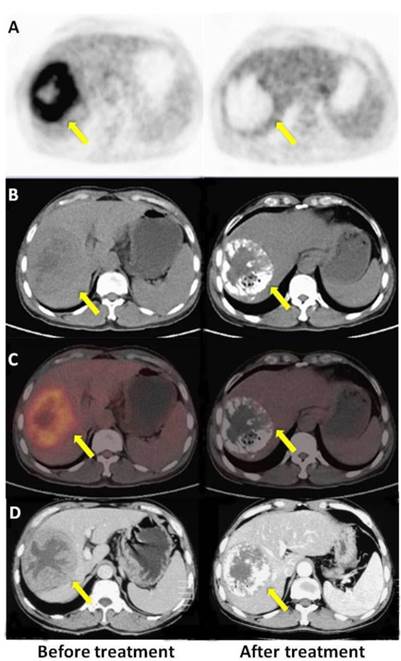

Figure 5

A: PET, B: CT, C: PET/CT fused axial images, and D: enhanced CT. A 60-year-old male with HCC (once TACE, OS 24.6 m, mRECIST CR, PET response). The time elapsed after TACE was 31 d for enhanced CT and 32 d for the PET/CT scan, respectively. Compared with high tumor uptake in the first PET scan (left), there was no 18F-FDG uptake in the tumor or surrounding tissue in the second scan (right). Both PET/CT and enhanced CT indicated a good response to treatment.